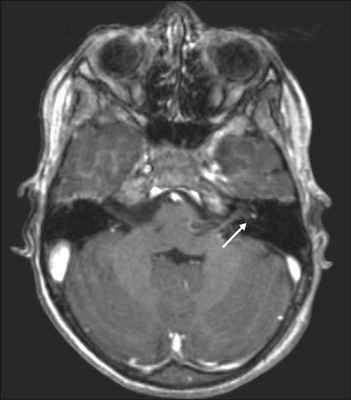

Косвенные признаки ВН можно выявить при использовании высокопольной магнитно–резонансной томографии головного мозга с гадолинием.

Усиленный МР-сигнал от левого вестибулярного нерва у пациента с ВН (МРТ с контрастированием, гадолиний)